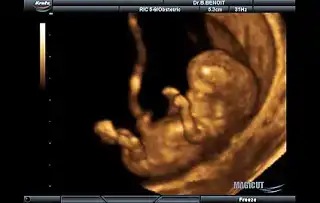

Ay canım evet, bana da doktor 12. haftamda erkeğe benziyor demişti ama çok belirsiz söylemişti. Bana sanki kızmış gibi geliyor. ikili testte kalp atışı falan da 180 çıktığı için kız olduğunu düşünüyorum ama doktor kafamı karıştırdı :) Şimdi kesin olarak öğrenmek için paşa paşa bekliyorum :) Erken tahminde insan pek tatmin olmuyo zaten.

tahmin işte bazen tutuyor bazen tutmuyor. benim bir arkadaşa doktor 6 aay falan erkek demişti onlar da herşeyi mavi almaya başlamıştı son aylara doğru kız dediler. insan kötü oluyor. umarım Allah herkese gönlünden geçen sağlıklı bebekler verir